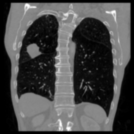

Aside from quantitative results, we provide a principal component analysis (PCA) visualisation of the 3D embeddings of Merlin, CT-FM, CT-CLIP, and our COLIPRI-CRM encoder, on a lung cancer case from the MSD Lung dataset (Fig. 1). The embedding resolution is very low for Merlin and CT-FM, providing hardly any semantic localisation. CT-CLIP yields embeddings of higher resolution, allowing features to be visually mapped from the input CT to the PCA map. However, the PCA map is inconsistent and noisy, and exhibits a strong bias towards absolute position within the scan, as visible through the anteroposterior green/red shift. On the other hand, our COLIPRI encoders yield higher-resolution embeddings, which are sharper and more consistent, allowing for clear recognition of the boundaries of the patient, lungs, and the abdominal organs, as well as the lung mass present in the right lung (on the left-hand side of the coronal and axial slice views).